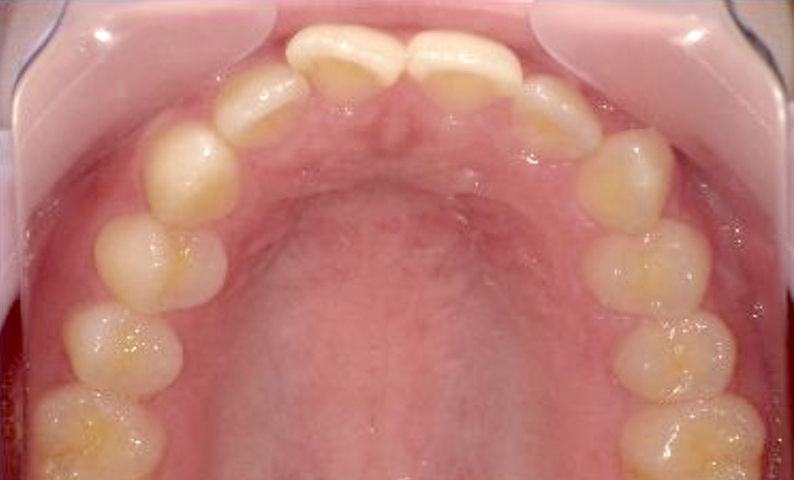

症例_001 上下顎の部分矯正

治療期間:12ヶ月金額:54万円+税女性前歯のガタガタ逆八の字

| Before | After |